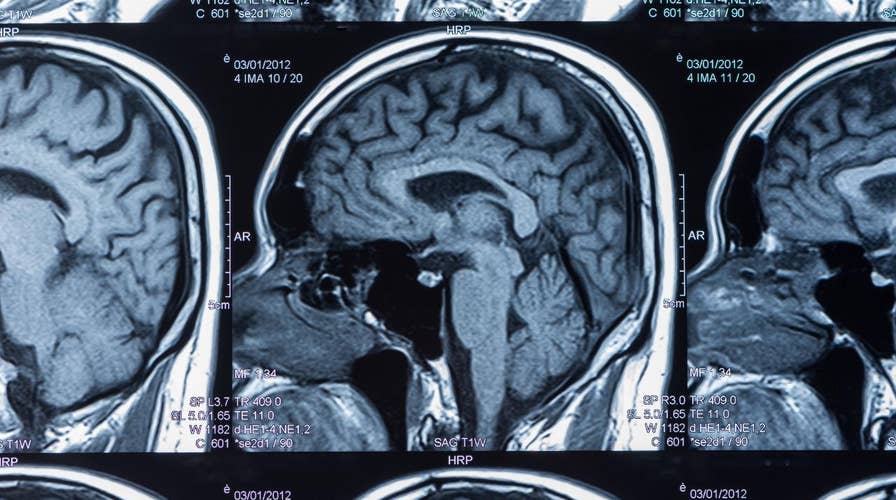

First CTE diagnosis on living NFL player confirmed by autopsy, report shows